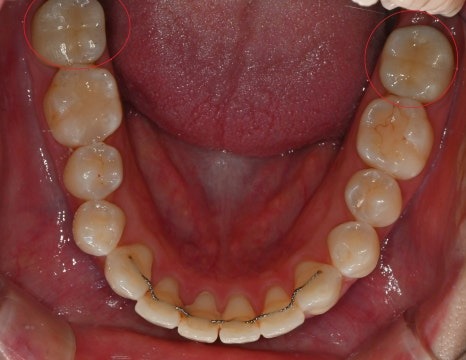

크라운 치료 전

크라운 치료 후

· 20대 여성 환자

치과 공포증으로 치료를 미루다 충치 진행

→ 수면으로 양측 어금니 크라운 치료 및

매복 사랑니 발치 동시 진행